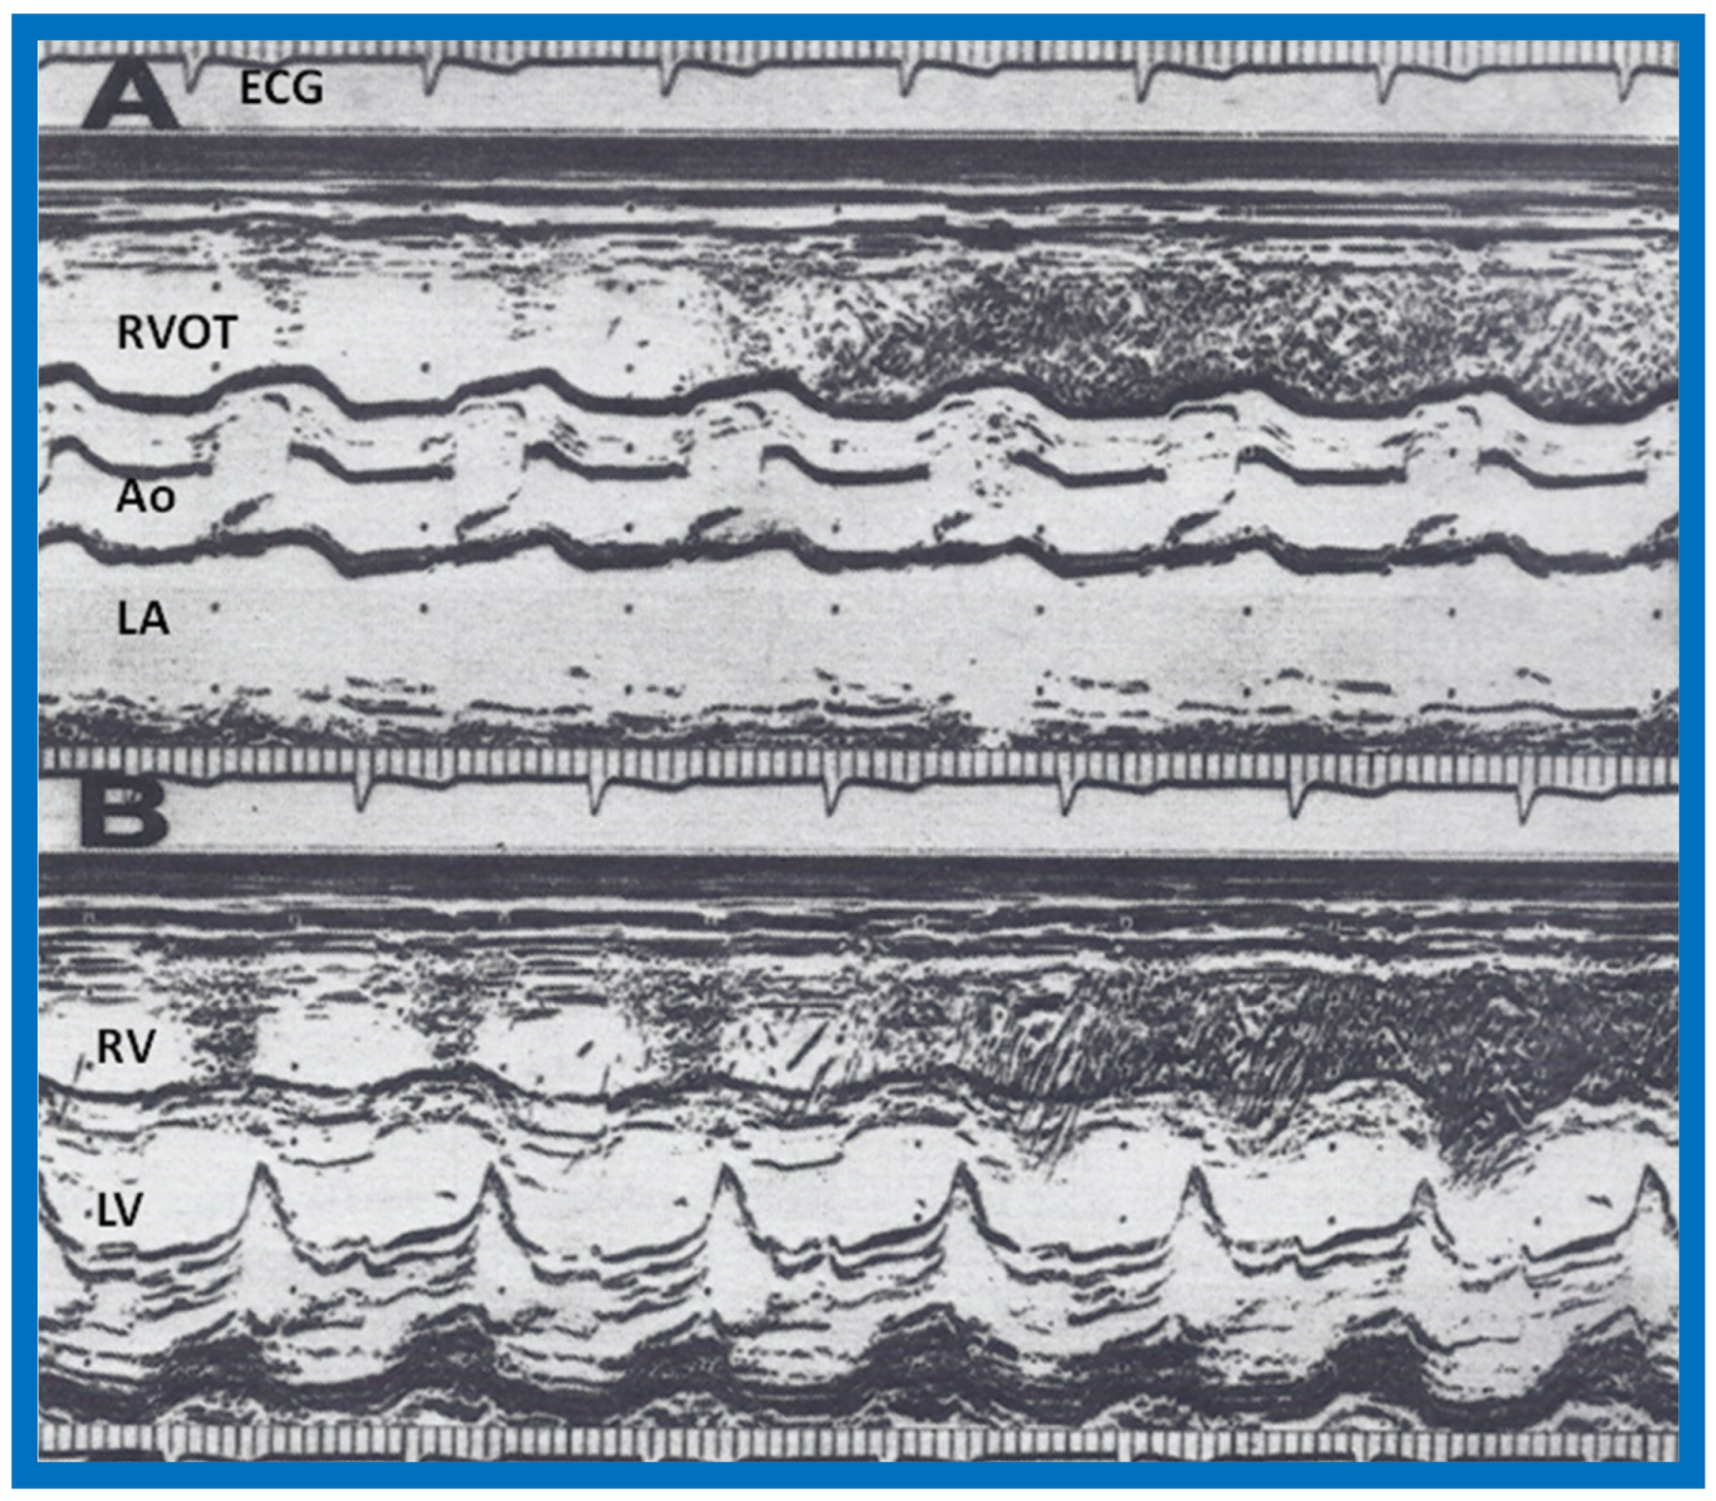

We presented the methods of measurements/calculations of systolic time intervals (Figure 11 and Figure 12), left ventricular volumes, LV shortening fraction (Figure 13), LV velocity of circumferential fiber shortening (Vcf), percent thickening of the LV posterior wall (Table 1) and their utility in the evaluation of LV function. This was followed by a discussion of diastolic function of the LV, other indices of LV function, LV function in aortic stenosis, LV function in LV volume overloading conditions and congestive cardiomyopathy. Then, newer methods (as of early 1980s) of assessing LV function by two-dimensional echocardiography, Doppler ultrasound-measured aortic blood flow velocity and radio-nuclide ejection fraction were briefed. The papers were concluded by outlining the value and limitations of noninvasive technology, as they were at that time [5,6].

Figure 12.

(A) Selected M-mode recordings from the parasternal short axis view of the left atrium (LA), aorta (Ao), and right ventricular outflow tract (RVOT) illustrating measurements of preejection period (PEP) and ejection time (ET). (B) Selected M-mode recordings from the parasternal short axis view of the left ventricle (LV) and right ventricle (RV) showing mitral valve closure and Q-Mc (Q wave of the electrocardiogram (EKG) to mitral valve closure). Isovolumic contraction time (ICT) is calculated by subtracting Q-Mc from PEP, ensuring that both recordings are made from cardiac cycles of identical length. Modified from Rao P.S., Kulangara R.J. [5].

Figure 13.

Selected M-mode recording from the parasternal short axis view of the left ventricle at the tips of the mitral valve illustrating measurements of left ventricular end-diastolic (LVEDD) and end-systolic (LVESD) dimensions to calculate shortening fraction (see Table 1). Reproduced from Rao P.S., Kulangara R.J. [5].